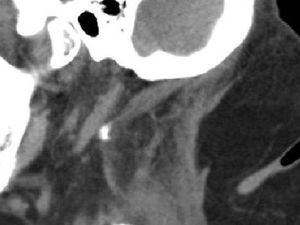

detikHealthSelasa, 09 Feb 2016 11:04 WIB Tumbuh 'Punuk' Akibat Kecanduan Alkohol Seorang wanita di AS mempunyai 'punuk' seperti kerbau. Ia terserang Madelung Disease, penyakit yang sangat langka akibat kecanduan alkohol.